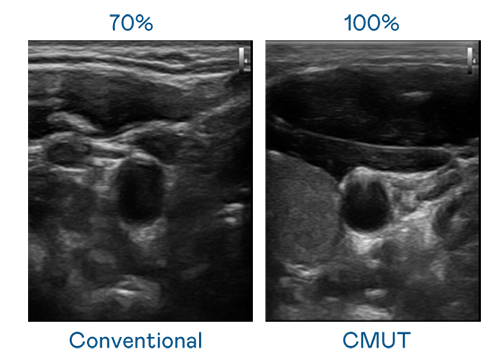

CMUT 技术是一种用电容式微机电元件来产生超音波讯号的技术。与传统 PZT 压电式技术相比,CMUT 频宽增加 30%,更宽频的超音波讯号让影像解析度大幅提升,是实现高影像品质医疗超音波扫描、促进精准医疗发展的关键技术。

大频宽带来超清晰影像

超音波影像的解析度高低,首先取决于探头能发出的讯号频宽。米兰milan CMUT 可提供高清晰的超音波讯号,提供高频宽、高灵敏度、影像纹理细节更高的超音波影像,协助医护人员缩短影像判读时间及利用精准的医疗影像进行诊断。